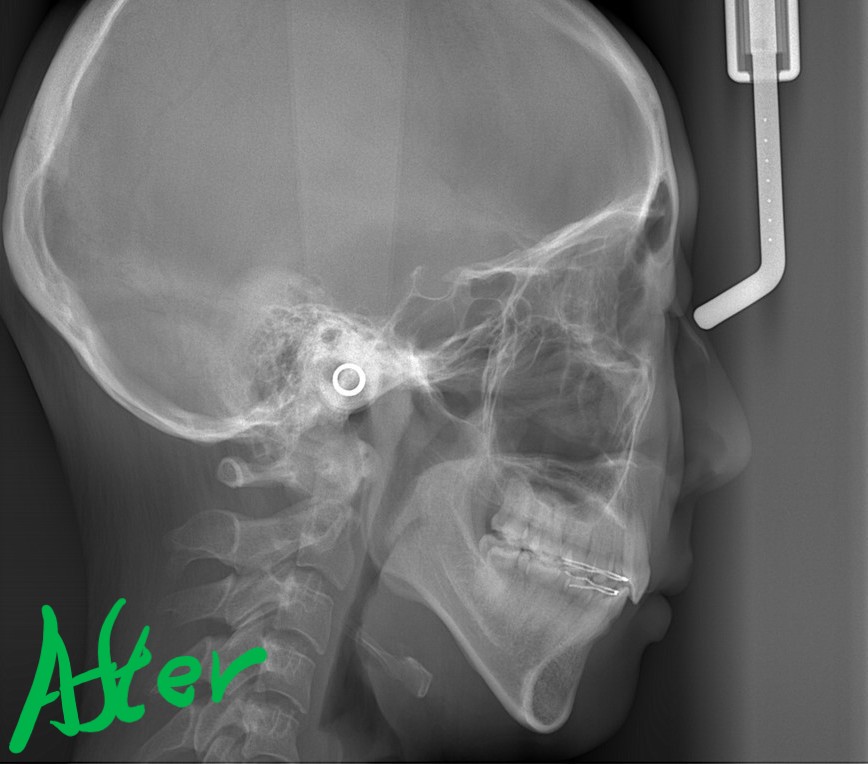

【After】

矯正後の状態をレントゲン写真で確認すると、

【治療期間】 2年5カ月間

・ハーフホワイトtypeのマルチブラケットシステム

・アンカースクリューを2本

・PLAS&パラタルバーを使用 【抜歯】

上下の左右の奥歯を1本ずつの計4本を抜歯

歯並びがキレイになったことはもちろん、口元や横顔もスッキリさせることができました。

Eラインに収めることは出来ませんでしたが、お口を閉じる時の緊張もほぼ無くなり、「楽にお口を閉じることが出来るようになった!」と喜んでもらえました。